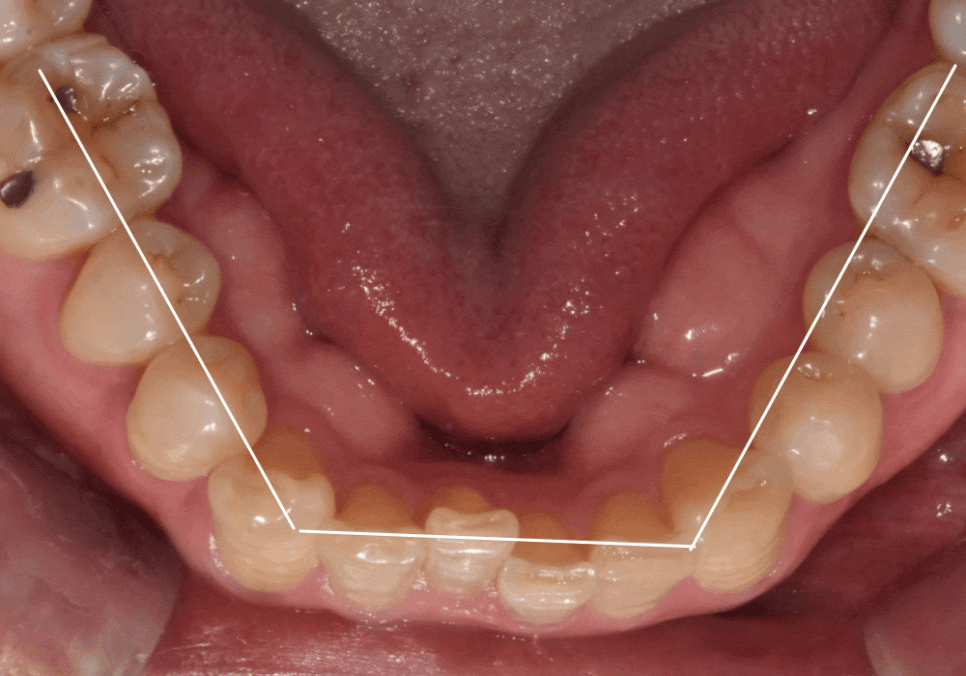

이번 사례의 환자분은

아래 중앙 앞니(#41) 하나가

혼자만 안으로 쑥 들어가 있어

배열이 어긋나 보이는 게

가장 큰 고민이셨습니다.

치아 라인을 위에서 내려다보니

매끄러운 U자 아치형이

앞니로 인해

'ㄷ' 자로 꺾인 모습이었습니다.